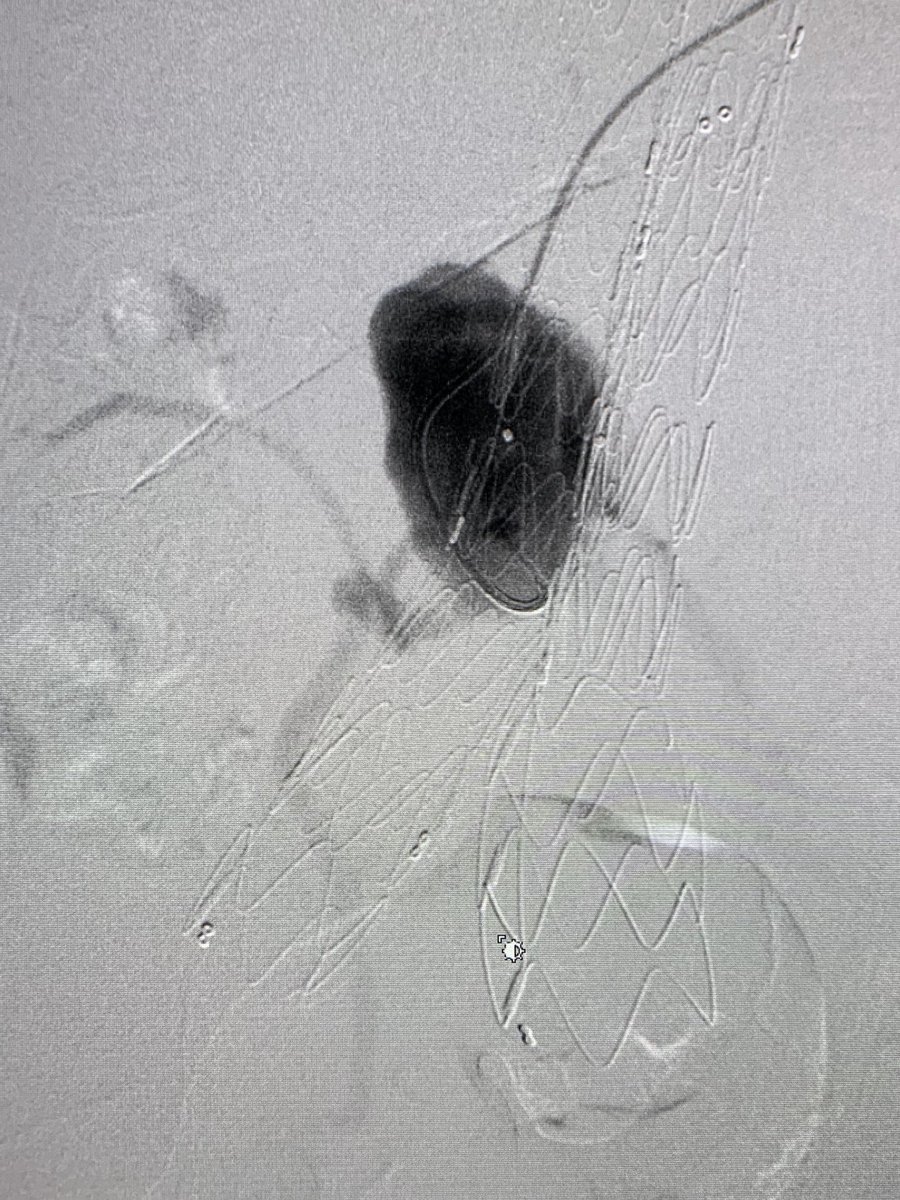

Nothing exotic but love treating popliteal aneurysms the endovascular way.

@SIRspecialists@SIR_ECS@AVIRnews@JVIRmedia@AMPSymposium@cvirendo@EVToday@NCVHonline#popliteal#aneursym#viabhan#irad#interventionalradiology#angiogram#percutaneous pic.twitter.com/KN0TbRwZdl